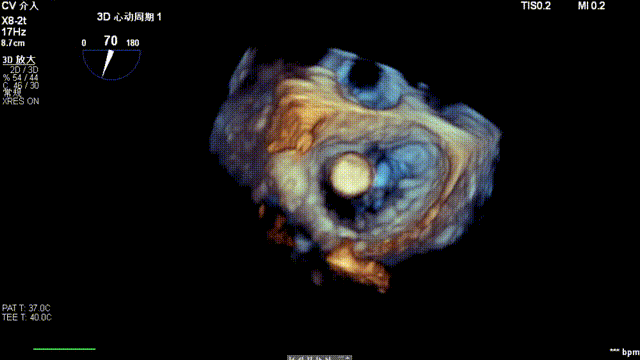

术后超声

最终在A3P2位置夹合,前叶夹合量10mm,后叶夹合量8mm,剩余瓣口面积3.45cm²,平均跨瓣压差2mmHg,反流基本消除。